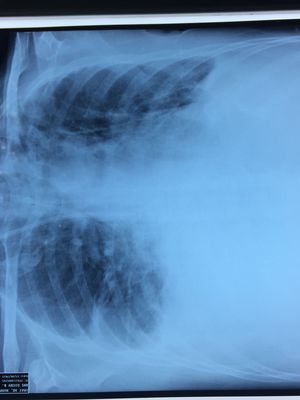

Guess the diagnosis

Bilateral pleural effusion more on R-site